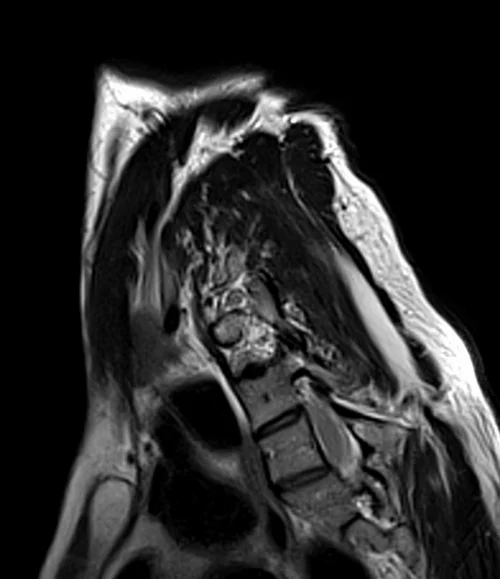

MRI brachial plexus sagittal oblique T2 images